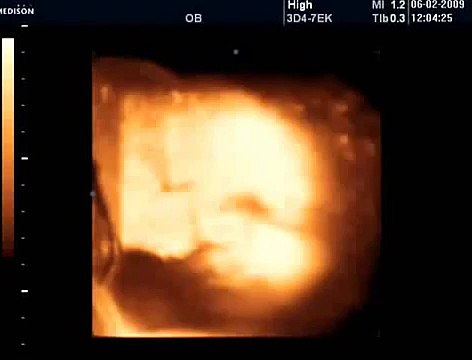

KAYSERİ'nin Yeşilhisar ilçesinde 2,5 yıl önce tüp bebek yöntemiyle sahip oldukları Saliha Çakır'ı (4) nar zehirlenmesinden kaybeden Üzeyir Çakır (39) ve eşi Kevser Çakır (44) aynı yöntemle yeniden bebek sahibi olmak istiyor. Kevser Çakır, Biz 15 yıllık evliyiz. Tüp bebek yöntemiyle bir kızımız dünyaya geldi. O da nar zehirlenmesi nedeniyle hayatını kaybetti. Şimdi yeni tedaviye başladık. Şuan çok mutluyum dedi. Olay, 30 Ekim 2019'da Yeşilhisar ilçesi Kavak Mahallesi'nde meydana geldi. Çakır ailesi, akşam yemeğinden sonra nar yedi. Bir süre sonra baba Mustafa (67), eşi Saliha (61), oğulları Osman (26), Üzeyir (36), eşi Keser (44) ve çocukları Saliha Çakır, rahatsızlandı. 6 kişilik aile, komşularının yardımıyla karın ağrısı ve baş dönmesi şikayeti ile Yeşilhisar Devlet Hastanesi'ne kaldırıldı. İlk belirlemelere göre, gıda zehirlenmesi şüphesiyle aile fertlerine serum tedavisi uygulandı. Küçük Saliha, durumu kötüye gidince Kayseri Şehir Hastanesi'ne sevk edildi. Haber</a> haberler.com/tup-bebek-saliha-yi-nar-zehirlenmesinden-kaybeden-14815567-haberi/